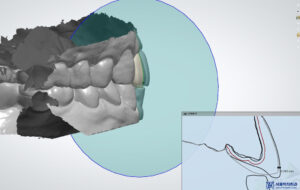

원내 기공소에서 크라운

제작을 진행하였습니다.

본원 자체 운영 중인 원내기공소에서

1:1 개인 맞춤형으로

크라운을 제작하고 있습니다.

10년 차 이상의

치과기공사 실장님이 상주하며,

정교하고 세밀하게 디자인하여

보철물을 제작합니다.

또한 저작하는데 편하실 수 있도록

기능적인 면뿐만 아니라,

전체적으로 자연치아 모양과 색 등

자연스럽게 구현이 가능하도록

전문적으로 작업을 하고 있습니다.